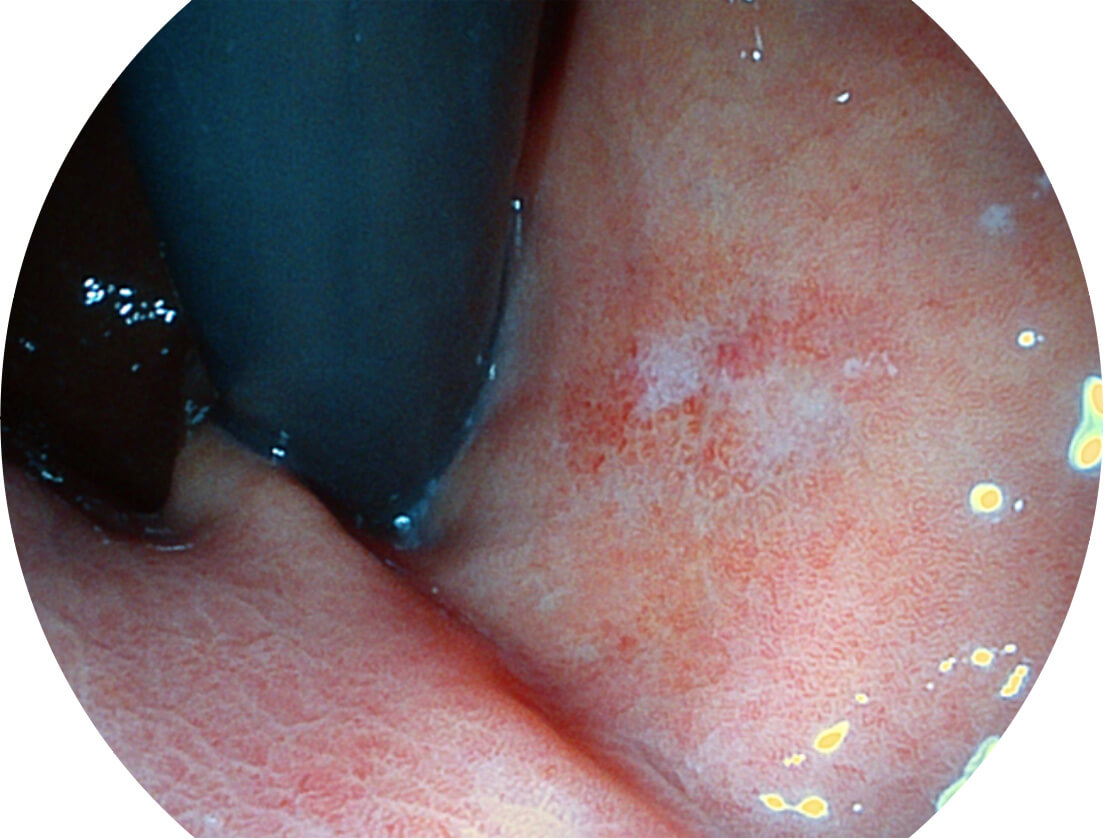

白光图像

VIST图像